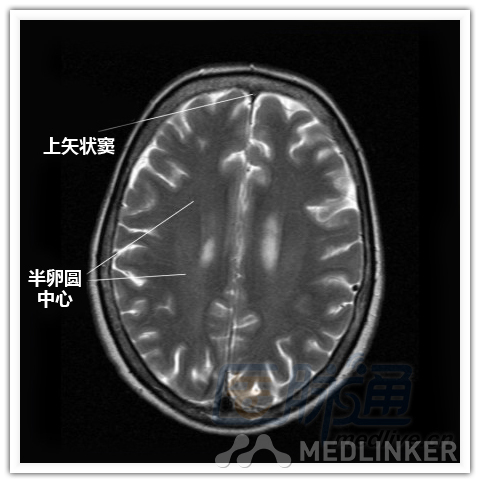

本文将对不同横断位的脑部MRI图像进行标示,主要讲解内容是脑部基本解剖。脑部横断位解剖,尤其是内囊层面的影像学解剖一直是一大重点,一起来学习一下。 现在是内囊层面了,同志们准备好了吗? 本文转载自医脉通。 声明:本文转载是出于提供更多信息以参考使用或学习、交流之目的,不用于商业用途。转载无意侵犯版权,如转载文章涉及您的权益等问题,请作者速来告知,我们将尽快做删除处理。